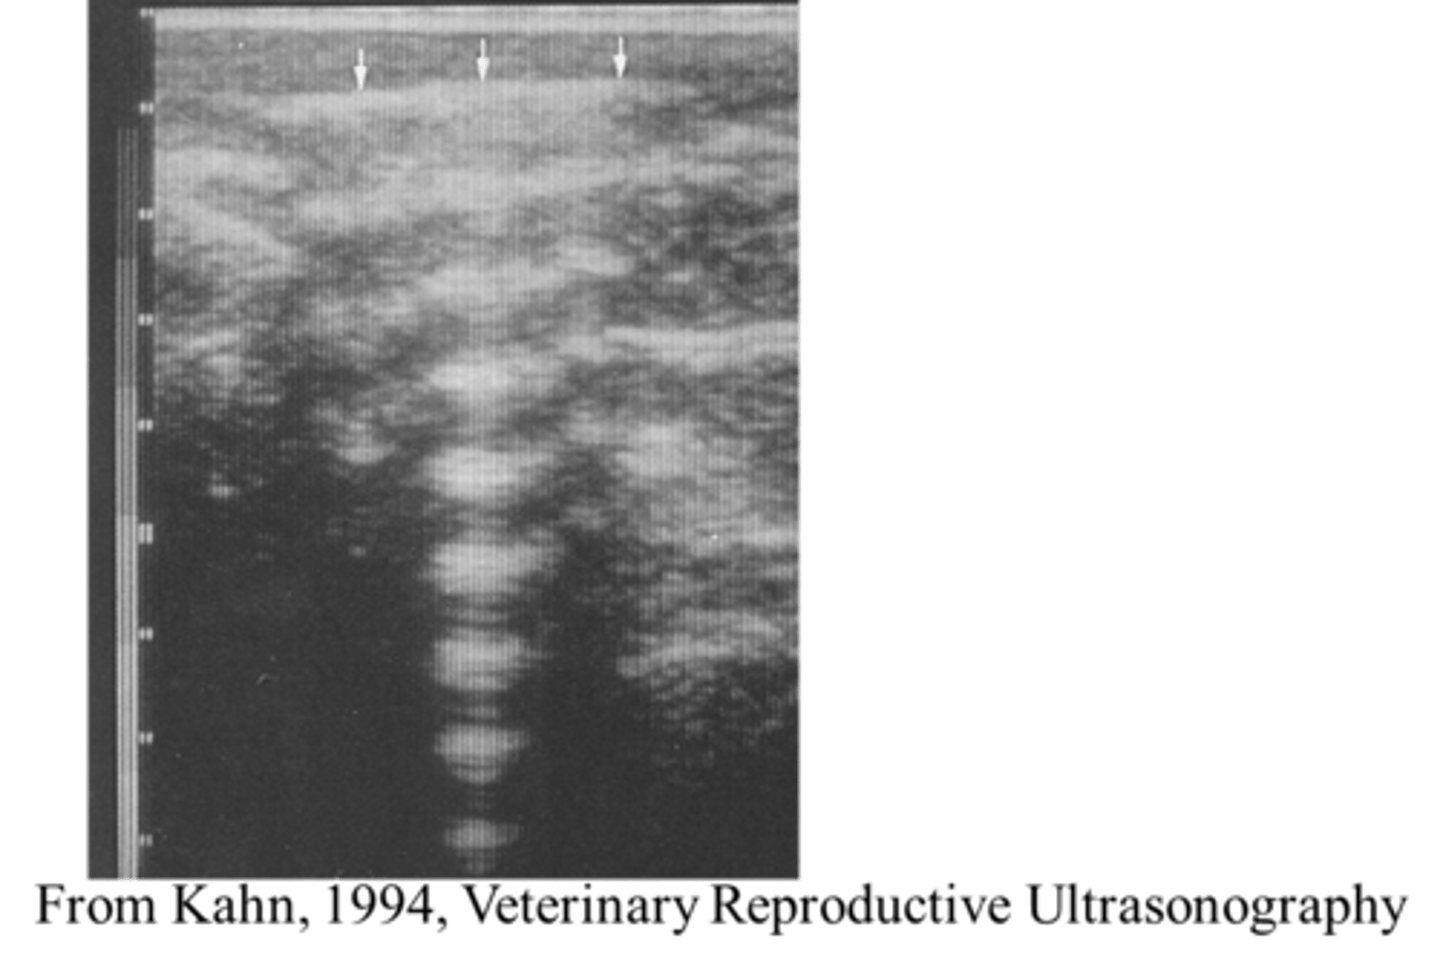

How is the reverberation artefact useful for follicles/vessels?

When the beam is perpendicular to a follicle or vessel, the reverberation artefact will consequentially cause the wall to become whiter.

<p>When the beam is perpendicular to a follicle or vessel, the reverberation artefact will consequentially cause the wall to become whiter.</p>

Why does acoustic enhancement cause artefacts?

If ultrasound waves travel through a structure which is less attenuating (absorbing) or a more transparent structure, the tissue of interest behind it may be shrouded due to more waves being transmitted through and hence reflecting back and reaching the scanner head. This causes false hyperechoic (white) regions to form.

<p>If ultrasound waves travel through a structure which is less attenuating (absorbing) or a more transparent structure, the tissue of interest behind it may be shrouded due to more waves being transmitted through and hence reflecting back and reaching the scanner head. This causes false hyperechoic (white) regions to form.</p>